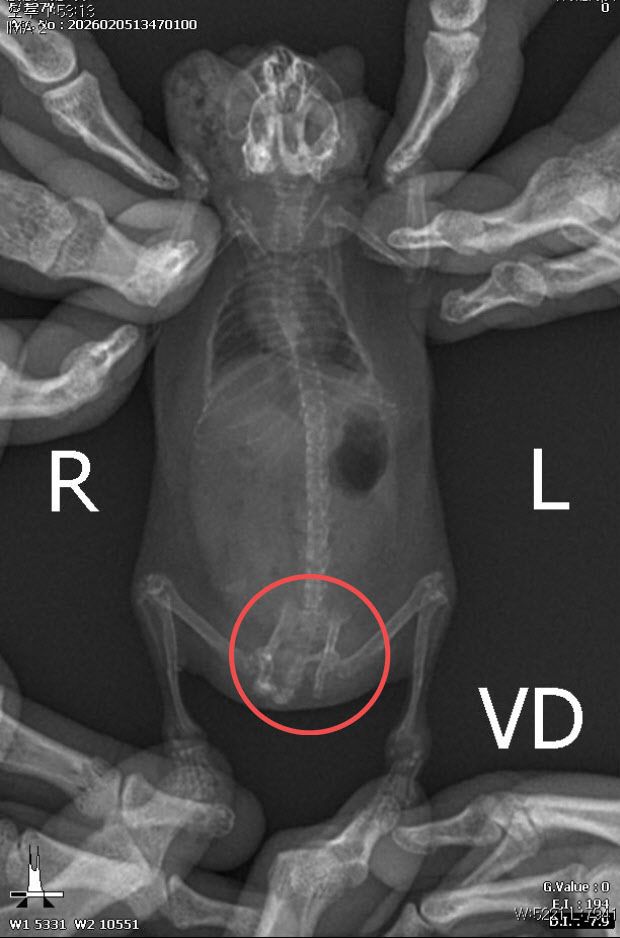

A씨는 지난 3월부터 최근까지 햄스터, 기니피그, 피그미다람쥐 등 소동물을 학대하고 그 장면을 촬영해 온라인 공간에 올린 등 혐의를 받는다.

햄스터는 동족 포식 습성(카니발리즘)을 지녀 합사할 경우 서로 공격해 다치거나 죽을 수 있는데 A씨는 여러 개체를 좁은 우리에 함께 키운 것으로 전해졌다.

성동경찰서에 고발장이 접수된 이번 사건은 A씨 소재지 파악 이후 울주경찰서로 이관됐는데 현장 점검 결과 22마리가 피학대 동물로 판단됐다.

피해 동물 22마리는 피그미다람쥐나 몽골리안 저빌, 펫테일 저빌 등으로 야생생물 보호 및 관리에 관한 법률상 보관 신고가 필요한 지정 관리 대상 동물이었음에도 아무런 조치가 이뤄지지 않은 것으로 파악됐다.

동물자유연대는 지난해 12월 제보 접수 이후 A씨를 동물보호법 위반 혐의로 고발했지만 A씨는 오히려 햄스터를 청소기로 빨아들이거나 통에 넣고 흔드는 등 학대 수위를 높였으며 ‘나는 무섭지 않다’는 글을 올린 것으로 드러났다.